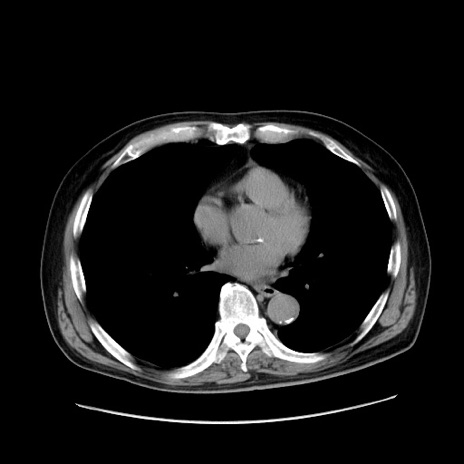

症例30(横断像)

【症例】80歳代男性

【主訴】臍周囲痛

【現病歴】約6時間前から臍下部痛が出現。次第に腹部膨隆・背部痛も生じてきたため来院。背部痛の場所は変化しない。

【身体所見】意識清明、BT 36.3℃、BP  131/87mmHg、P 87bpm、SpO2 100%(RA)、臍周囲自発痛・圧痛あり、反跳痛なし、自発痛部位に一致して板状硬あり、腹部膨隆、腸雑音減弱、CVA tenderness両側陰性。